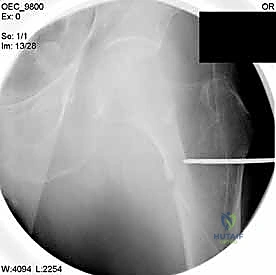

1. التجهيز والتخدير

يبدأ الأمر باختيار نوع التخدير المناسب (غالباً تخدير نصفي/شوكي لكبار السن لتقليل العبء على القلب والرئتين). يتم وضع المريض على "طاولة الكسور الخاصة" (Fracture Table)، وهي طاولة جراحية متطورة تسمح بشد الساق وتدويرها للوصول إلى الوضع المثالي.

2. الرد المغلق تحت جهاز الأشعة (Closed Reduction)

قبل إجراء أي شق جراحي، يقوم الدكتور هطيف بسحب الساق وتدويرها بمهارة فائقة لإعادة العظام المكسورة إلى مكانها الطبيعي (المحاذاة التشريحية). يتم التأكد من ذلك باستخدام جهاز الأشعة السينية المتحرك داخل غرفة العمليات (C-Arm Fluoroscopy). هذه الخطوة حاسمة، فالرد الجيد يعني التئاماً ممتازاً.

مجموعة من الصور الإضافية التي توضح مراحل دقيقة من العمل الجراحي المعقد الذي يجريه الأستاذ الدكتور محمد هطيف لضمان أعلى درجات الدقة الميكانيكية الحيوية: